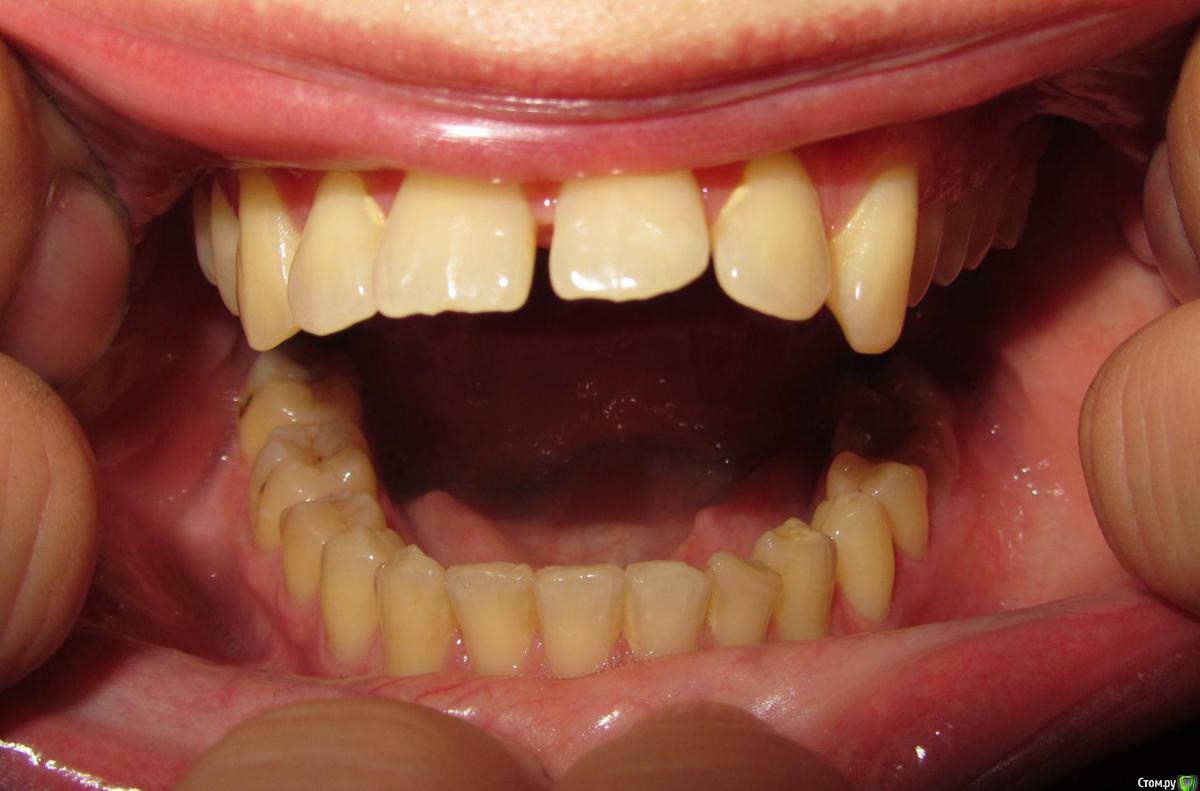

janis1 Опубликовано 14 ноября, 2015 Поделиться Опубликовано 14 ноября, 2015 Доброго времени суток, уважаемые профессионалы.Очень надеюсь на вашу помощь.Коротко о себе:37 лет, пол мужской. Так сложилось что в последнее время меня постигло сразу три проблемы,как мне кажется все они имеют между собой четкую связь. Основная проблема, с болями верхней челюсти, началась у меня около месяца назад. Боль не очень сильная, но практически постоянная. Боль не имеет какой-либо конкретной локации (болит именно вся челюсть). С утра она меньше, ближе к вечеру усиливается. В последнее время немного отдаёт в скулу. Одновременно с появлением боли, во рту, в районе дёсен, появился как бы привкус соды (немного похожий на вкус крови, но крови в ротовой полости нет).И в довершение всего начали катастрофически искривляются зубы верхней челюсти.На самом деле проблемы с прикусом у меня были уже с детства, примерно в 10 - 12 лет я носил пластинку для исправления прикуса.Но к сожалению лечение так и не закончил, соответственно прикус все это время у меня был неправильным, но до последнего времени он меня не беспокоил, так как был если так можно сказать "в пределах разумного", и в течении долгого времени был неизменен, но в последние несколько месяцев верхние зубы искривились настолько катастрофически что что я реально начал шепелявить. При попытке расшатывания зубы стоят крепко, не болтаются. Пока во всяком случае... Со всеми этими проблемами я пробовал обращаться к зубному хирургу и ортодонту,ни хирург, ни ортодонт к которым я обращался не смогли назвать каких-либо конкретных причин по которым может появляться боль в верхней челюсти и привкус во рту.Врачи к которям я обращался действительно хорошие специалисты, но похоже видят проблемы узко по своей специализации.Единственно хирург указал на то, что возможно придется удалять восьмерки, а ортодонт предложил установить брекеты на обе челюсти.Я прекрасно понимаю что с таким прикусом мне действительно не избежать установки брекетов, но меня беспокоит то, что не найдена причина происхождения всех проблем о которых я написал. Очень надеюсь на вашу помощь в поиске возможных причин проявления моих проблем. Заранее благодарен! Ссылка на комментарий

Jurai Опубликовано 22 ноября, 2015 Поделиться Опубликовано 22 ноября, 2015 Есть проблема во фронтальном участке верхней челюсти: общая убыль костной ткани, ячеистая структура кости. смещение зубов так, что корни изогнулись, это значит, что либо резорбция (рассасывание) либо очень длительное уже идет воздействие. Могу подозревать новооборазование в этом участке.Вам нужна консультация челюстно-лицевого хирурга-онколога. 1 Ссылка на комментарий